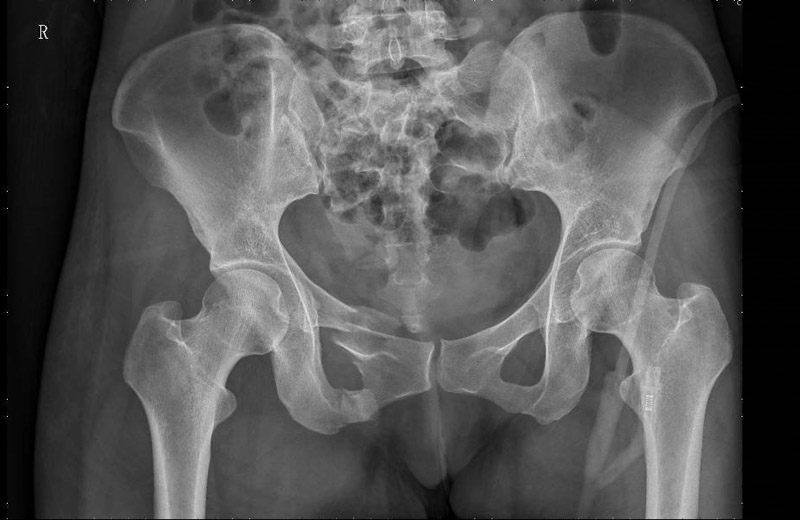

患者周女士在走路時不慎被車撞傷,被120送至當地醫院,清醒后感覺臀部劇痛難忍,雙髖活動受限,為求進一步治療,轉入了柳州市人民醫院創傷骨科,經CT檢查,患者為骨盆骨折,需手術治療。

骨盆位置深,內部臟器結構豐富,血管神經復雜,一旦發生損傷,常常導致相應的血管神經損傷和大出血,所以骨盆骨折手術一直被認為是創傷骨科中最復雜的手術之一。且傳統切開復位內固定手術對患者傷害較大,容易造成術中血管神經的損傷、術后感染等并發癥的發生。